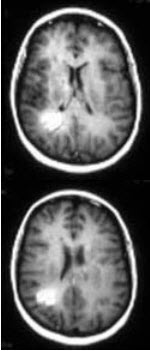

根据如图提示,多发性硬化MRI特点为( )

A:多个类圆形及其融合灶短T1,长T2

B:单个类圆形及其融合灶长T1,长T2

C:多个类圆形及具融合灶长T1,短T2

D:多个类圆形及具融合灶长T1,长T2

E:多个类圆形及其融合灶短T1,短T2